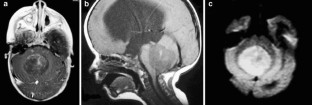

Fig. 2